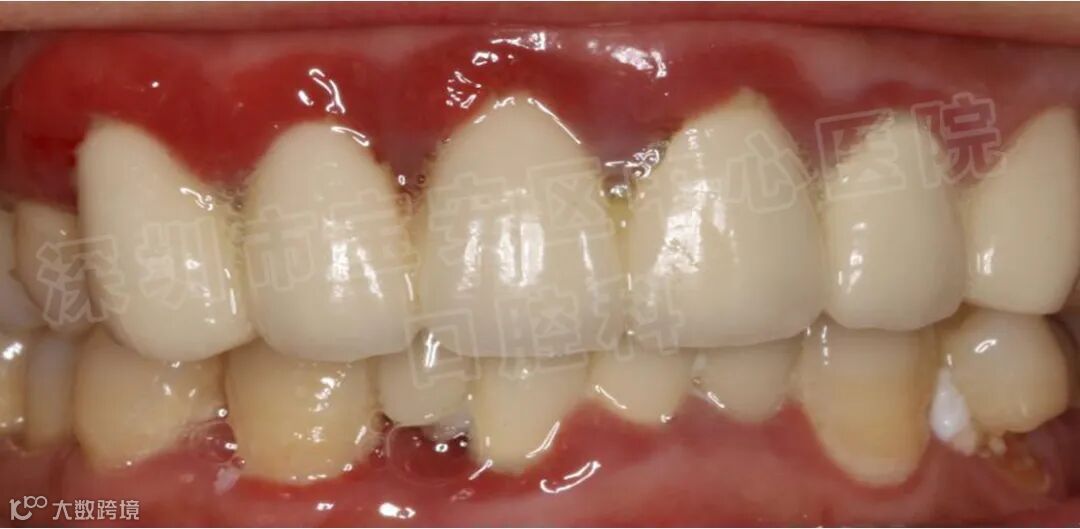

牙周基础治疗

龈上洁治、龈下刮治、根面平整等。

经过上述治疗之后,大多数患者的牙周炎症可以得到消除,松动的牙齿慢慢稳固,患者的咀嚼功能明显提高。但是,经过牙周基础治疗之后,部分患者仍然会有个别牙齿,甚至多颗乃至整个牙弓中的余留牙齿松动,难以行使正常的咀嚼功能,一旦出现上述问题,则需要采用牙周炎手术治疗。牙周翻瓣,牙周再生,骨再生等手术去恢复牙龈炎症,牙槽骨吸收等问题